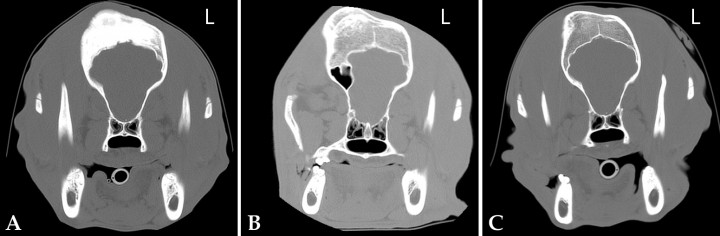

Se procedió a realizar una tomografía computarizada (TC) del cráneo. La adquisición de las imágenes se realizó en cortes de 1 mm de espesor, en dos series procesadas con filtros de tejido blando y hueso. Las imágenes se visualizaron en cortes de forma transversal junto con las reconstrucciones sagital y dorsal. En las imágenes obtenidas se observó una zona focal de reacción perióstica, fusiforme y compacta, en el hueso frontal derecho. Estas lesiones también estaban presentes, en menor intensidad, en el hueso frontal izquierdo. Esta proliferación ósea no presentaba márgenes nítidos, ni zonas de crecimiento de hueso en tejidos blandos, ni tampoco zonas de destrucción ósea descritas como osteólisis (Fig. 2A).

<p>Imágenes de Tomografía Computarizada en plano transversal realizadas en ventana hueso. (A) Momento del diagnóstico. El hueso frontal derecho se observa moderadamente engrosado, además se observa una reacción perióstica fusiforme y aumento de la densidad del hueso de forma heterogénea. (B) A los 6 meses después del diagnóstico; la lesión ósea presenta reducción de la atenuación ósea y remodelación en el hueso frontal derecho. (C) A los 2 años de edad del paciente. La lesión presenta una pequeña disminución de tamaño y reducción de la atenuación ósea respecto al estudio anterior.</p>

Imágenes de Tomografía Computarizada en plano transversal realizadas en ventana hueso. (A) Momento del diagnóstico. El hueso frontal derecho se observa moderadamente engrosado, además se observa una reacción perióstica fusiforme y aumento de la densidad del hueso de forma heterogénea. (B) A los 6 meses después del diagnóstico; la lesión ósea presenta reducción de la atenuación ósea y remodelación en el hueso frontal derecho. (C) A los 2 años de edad del paciente. La lesión presenta una pequeña disminución de tamaño y reducción de la atenuación ósea respecto al estudio anterior.

Transcurridos 6 meses se realizó una segunda TC en la que la lesión ósea se mantenía en dimensiones similares, pero con una disminución considerable de la atenuación ósea en comparación con la primera (Fig. 2B). Esta vez se procedió a realizar también una resonancia magnética (RM) para comprobar que la lesión no afectase a otras estructuras (Fig. 3). Se observó una dismorfia del hueso frontal derecho que deformaba el cráneo en ese lado, sin que existiera un crecimiento óseo hacia el interior de la cavidad craneal. El seno frontal derecho presentaba mayor tamaño, pero estaba normalmente neumatizado. No se observaron alteraciones en los demás huesos que configuran la bóveda craneal ni la base del cráneo. Respecto al parénquima cerebral, cerebeloso y tronco cerebral, no se observaron alteraciones estructurales ni de la señal valorables en las distintas secuencias realizadas.

A los 2 años de edad del perro y transcurridos 11 meses desde la última TC, cuando el animal ya estaba completamente desarrollado, se procedió a realizar una última TC únicamente para observar la evolución de la lesión (en este momento, el animal no presentaba ningún tipo de conducta anormal ni signos clínicos aparentes). Se observó que la lesión ósea había disminuido ligeramente de tamaño y presentaba una menor atenuación ósea que en la segunda TC (Fig. 2C).